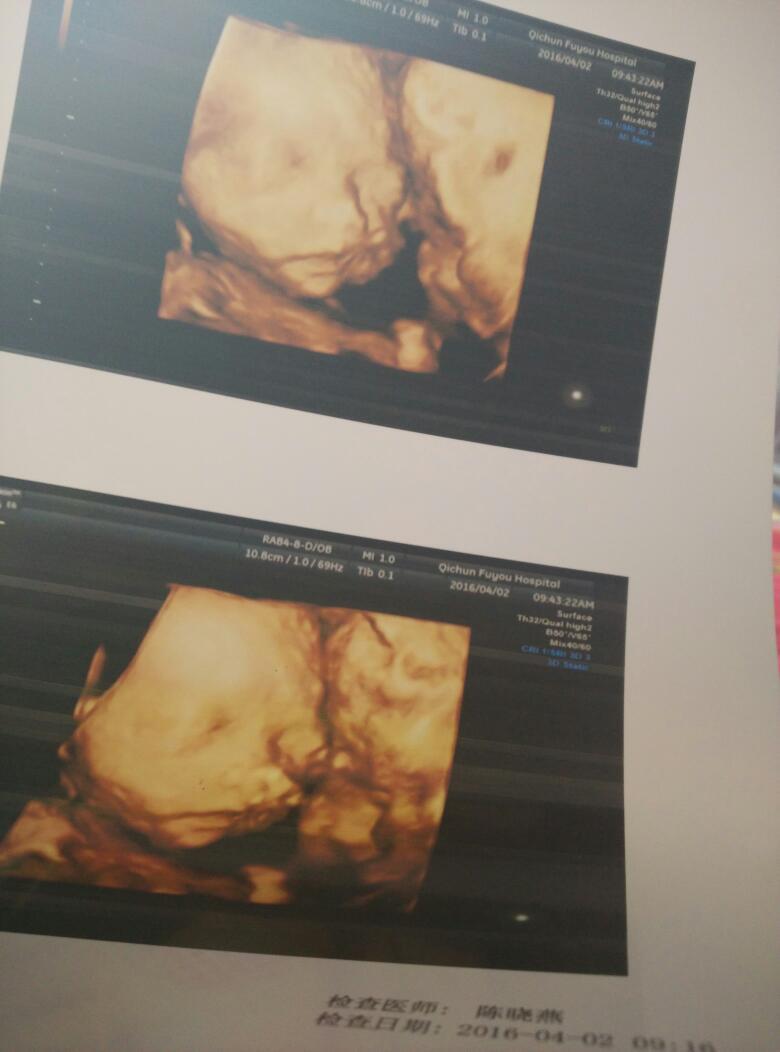

有没有谁看了懂我家宝宝是男孩是女孩呢

这就是我宝宝的数据

真希望宝宝是女孩